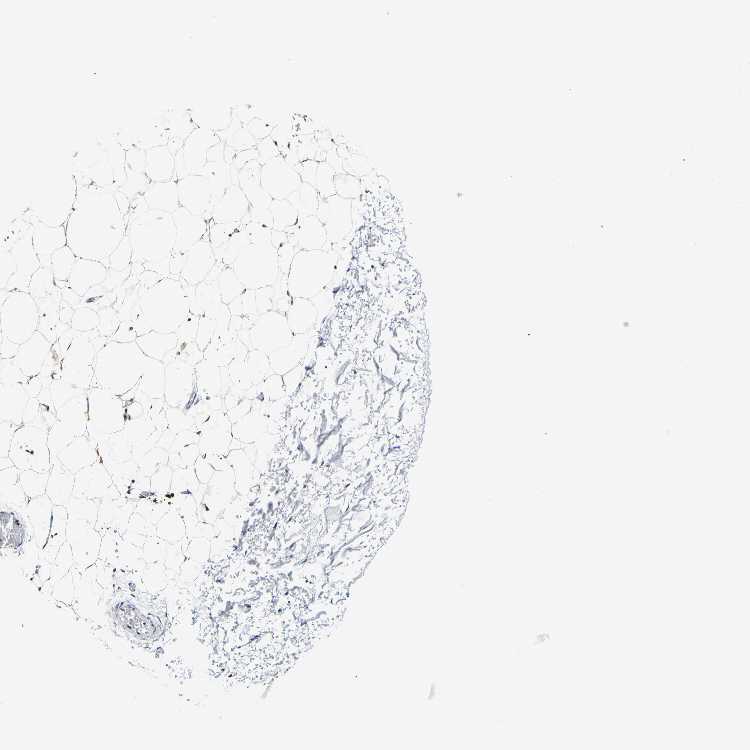

ADIPOSE TISSUE - Antibody stainingi

Antibody staining in the annotated cell types in the current human tissue is reported as not detected, low, medium, or high, based on conventional immunohistochemistry profiling in selected tissues. This score is based on the combination of the staining intensity and fraction of stained cells.

Each image is clickable and will lead to virtual microscopy that enables deeper exploration of all samples and also displays staining intensity scores, fraction scores and subcellular localization as well as patient and tissue information for each sample.

Antibody HPA018884Antibody CAB012463

Adipocytes MediumMedium